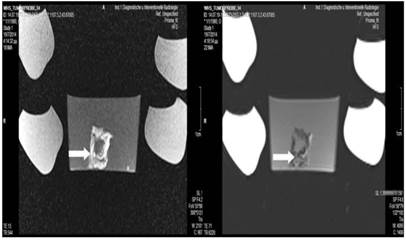

Figure 8

Lipidiolol and cisplatin; T1 sequence: Heterogeneous appearance in the central part of the tumor, low intensity indicates necrosis. T2 sequence: High signal intensity indicates necrosis. White formations are lipiodol molecules entrapped within the tumor tissue (white arrows).

Tumor necrosis and apoptosis were the major purposes of our study. Survival was also recorded. Our records and MRI findings indicate that a major toxicity was observed in the group where cisplatin, lipiodol and microwave were applied. None of the animals survived more than a week. Moreover; hemorrhage apart from necrosis was observed inside the tumors. Survival was the following for the groups: microwave (25days) ≥ cisplatin (22 days) > control (20 days) > lipiodol (16 days)> microwave plus lipiodol (16 days) > cisplatin plus lipiodol (12) > cisplatin plus microwave (12 days) > lipiodol plus cisplatin plus microwave (5 days). (Figure 5-12.)